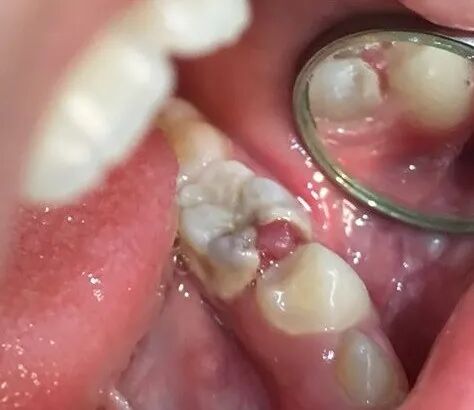

当查及患牙深洞有息肉时,临床上还要与牙龈息肉和牙周膜息肉相鉴别。牙龈息肉多是牙龈乳头向龋洞增生所致。牙周膜息肉发生于多根牙的龋损发展过程中,不但髓腔被穿通,而且髓室底亦遭到破坏,外界刺激使根分叉处的牙周膜反应性增生,息肉状肉芽组织穿过髓底穿孔处进入髓腔,外观极像牙髓息肉。在临床上进行鉴别时,可用探针探察息肉的蒂部以判断息肉的来源。当怀疑是牙龈息肉时,可自底部将其切除,见出血部位在患牙邻面龋洞龈壁外侧的龈乳头位置即可证实判断。当怀疑是牙周膜息肉时,应仔细探察髓室底的完整性,摄X线片可辅助诊断。一旦诊断是牙周膜息肉,应拔除患牙。

当查及患牙深洞有息肉时,临床上还要与牙龈息肉和牙周膜息肉相鉴别。

牙周膜息肉发生于多根牙的龋损发展过程中,不但髓腔被穿通,而且髓室底亦遭到破坏,外界刺激使根分叉处的牙周膜反应性增生,息肉状肉芽组织穿过髓底穿孔处进入髓腔,外观极像牙髓息肉。

在临床上进行鉴别时,可用探针探察息肉的蒂部以判断息肉的来源。当怀疑是牙龈息肉时,可自底部将其切除,见出血部位在患牙邻面龋洞龈壁外侧的龈乳头位置即可证实判断。当怀疑是牙周膜息肉时,应仔细探察髓室底的完整性,摄X线片可辅助诊断。一旦诊断是牙周膜息肉,应拔除患牙。